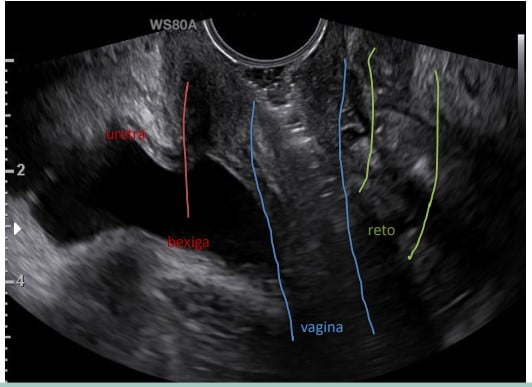

Na ginecologia, usa-se este exame de duas formas: via abdominal e via transvaginal. O primeiro deles é mais utilizado para órgãos da parte inferior do abdome e o segundo para avaliar o colo, ovários e trompas de falópio.

Usa-se o ultrassom ginecológico para avaliar os órgãos pélvicos, tais como útero, ovários, trompas de falópios e cavidade pélvica. Através das imagens obtidas, é possível reconhecer distúrbios uterinos, como miomas, pólipos endometriais, malformações anatômicas; cistos ovarianos, reserva ovariana, monitoramento da ovulação. Além disso, pode ser utilizado para confirmação inicial da gravide e diagnóstico de gravidez ectópica.

A escolha do método (transvaginal ou transabdominal) deve ser baseada nas características da paciente e no objetivo do exame. De forma geral, utilizamos via abdominal a baixa frequência, com resolução fraca porque possibilita boa visão geral e uma avaliação abdominal mais adequada. Já no ultrassom transvaginal, utiliza-se uma frequência alta para se ter uma resolução boa de estruturas próximas e pequenas.